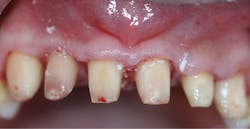

Once local anesthesia was achieved, the crowns were removed. Pulp exposures were noted in all teeth, necessitating root canal therapy (figure 3). Once the six teeth had received root canal therapy, the access openings were restored with a flowable, dual-curing, nano-hybrid core build-up material (Grandio Core Dual Cure, Voco). The teeth were prepared to correct margins while respecting surrounding periodontal structures. In order to allow the inflamed soft tissue to heal, a provisional “one-unit” bridge was fabricated and allowed to remain for six weeks (figure 4). A cold-cure composite provisional material was used (Structur 3, Voco), providing an elastic phase and allowing easy removal from the prepared teeth. The high gloss offered an ideal margin for the healing of inflammatory soft tissue, and elevated compressive strength and fracture resistance meant the patient could function in the provisional for longer periods of time.

Figure 3: Pulp exposures noted in all teeth